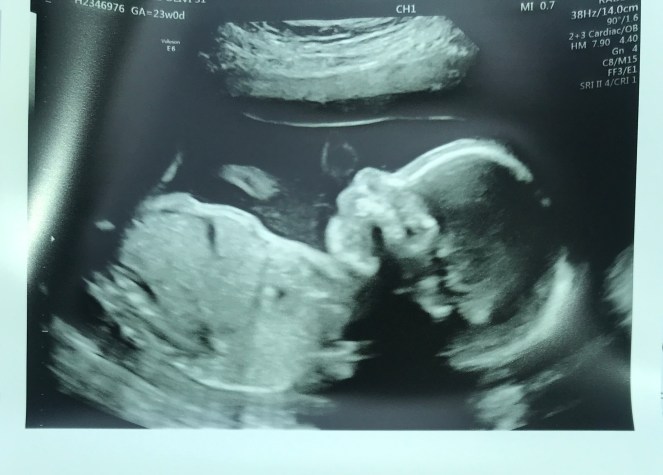

We had an appointment last week, and as usual, I was excited to see our baby’s growth and to see if any changes had occurred. The specialist that we saw this time was one we had never seen before, in fact she was new to the practice. When she entered the room, asked a few questions then proceeded to tell us what she saw on the ultrasound. The baby had not moved up at all from the last time, which meant that I still had complete placenta previa going on, but she has continued to grow right on schedule. There was no mention about the hematoma, so I decided to ask a few questions. She told us that it wasn’t a big concern at this point, but didn’t give us any real indication of if it had grown, stayed the same or shrunk. I also asked questions about my bed rest to get her opinion on the matter. To my surprise she had a very different mindset about bed rest, and went as far as to tell us that she didn’t believe in it. In her words, “studies have not shown bed rest to be an affective way to prevent pregnancy complications.” This was shocking to hear, and me being the eager type that wants to get moving again, wanted that to be true. Thankfully my level-headed husband was in the room to calm my excitement and to ask more questions.

Bed rest has continued and I saw my regular OB earlier this week. She confirmed that she highly disagrees with what the specialist said, and that we made the right decision to continue with the plan. She explained that too much movement can cause irritation to my cervix and in turn could result in another bleed or cause contractions. The last thing we want at this point is to be put in the hospital to prevent an early delivery. Even though 24 weeks is considered viability, the baby could have major life long issues, and we need to keep her in there as long as possible. We discussed getting things lined up for a planned C-section in early July and ensuring that we have all of our ducks in a row. It’s hard to believe that our little miracle will be here in roughly 3 months or so. Time has passed slowly, but at the same time I can’t believe that we have hit the 6 month mark and she will be here before too long.